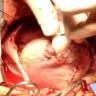

This video demonstrates the repair of a post-infarction ventricular septal defect.